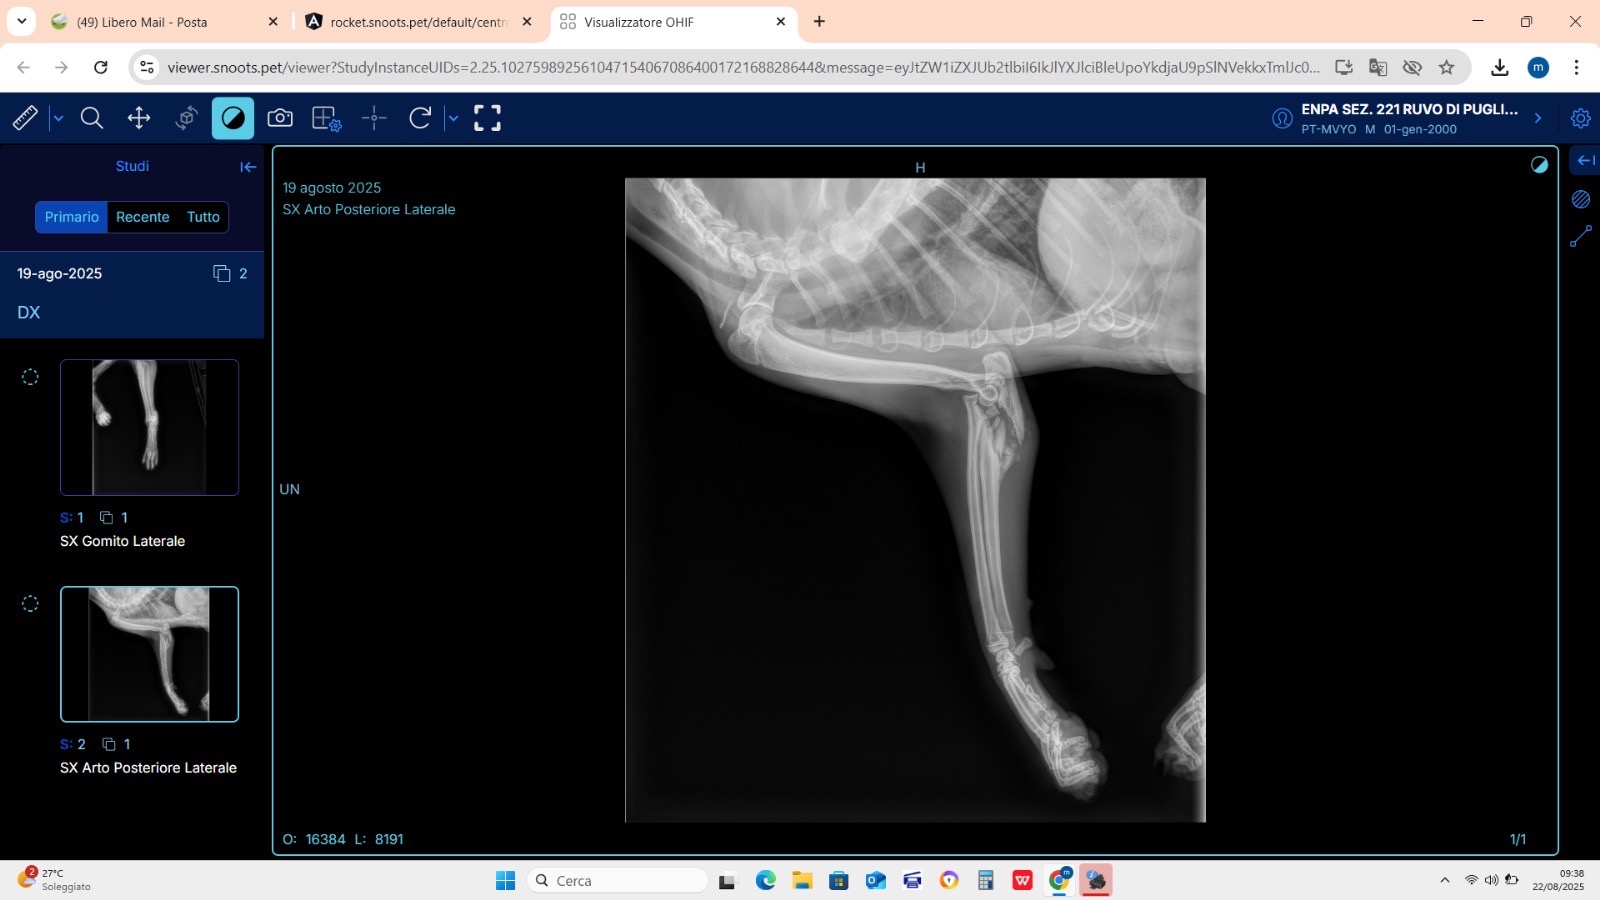

Dopo alcuni giorni di assenza, è stato ritrovato in condizioni gravissime: denutrito, stremato e con una profonda ferita alla zampa posteriore sinistra. Anche la zampa anteriore dello stesso lato risultava compromessa e il piccolo riusciva a malapena a muoversi.

Dopo le prime cure con antibiotici e antinfiammatori, sono stati effettuati esami più approfonditi. Purtroppo i raggi hanno rivelato la presenza di fratture complesse sia alla zampa anteriore che a quella posteriore sinistra. Si tratta di lesioni scomposte e difficili da trattare, che richiedono un intervento ortopedico molto delicato.